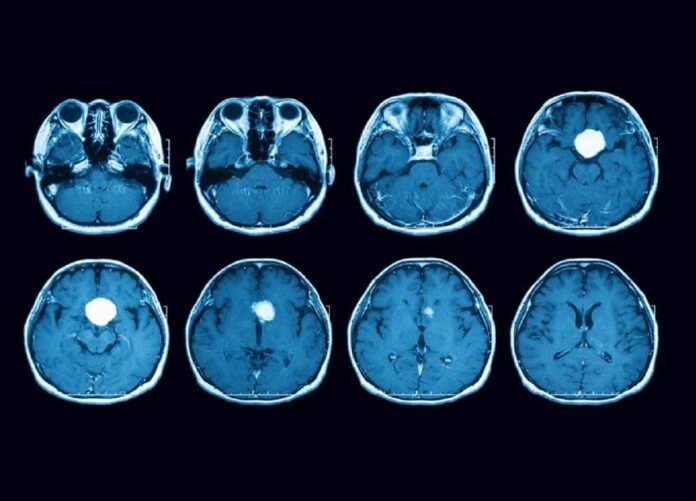

بر اساس شکایات ثبتشده، بسیاری از زنان به دلیل عدم اطلاع از این خطرات، سالها به مصرف این دارو ادامه دادهاند و در موارد متعددی، ابتلا به تومور مغزی منجر به انجام جراحی مغز، پرتودرمانی یا مراقبتهای عصبی مداوم شده است.